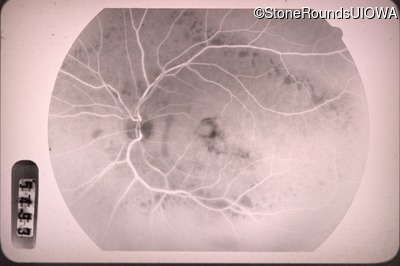

Fluorescein Angiography - Right - 20/100 -1

Exemplar